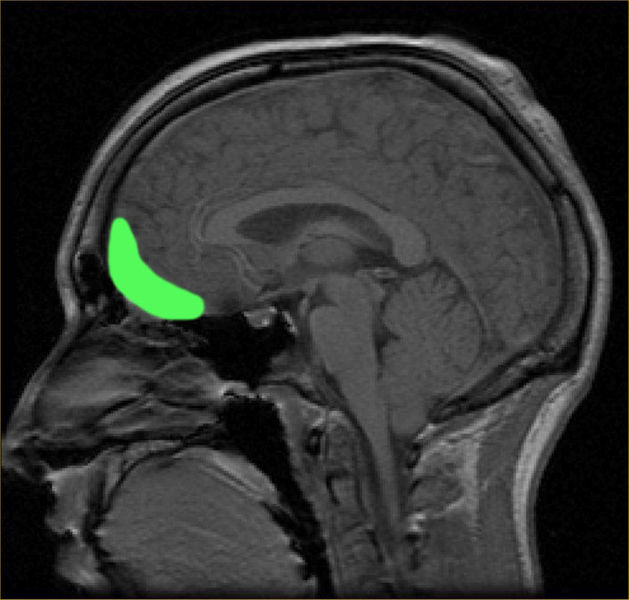

Antonio Damasio and his wife Hanna (also a neuroscientist and his academic partner) with their MRI scanner at USC.